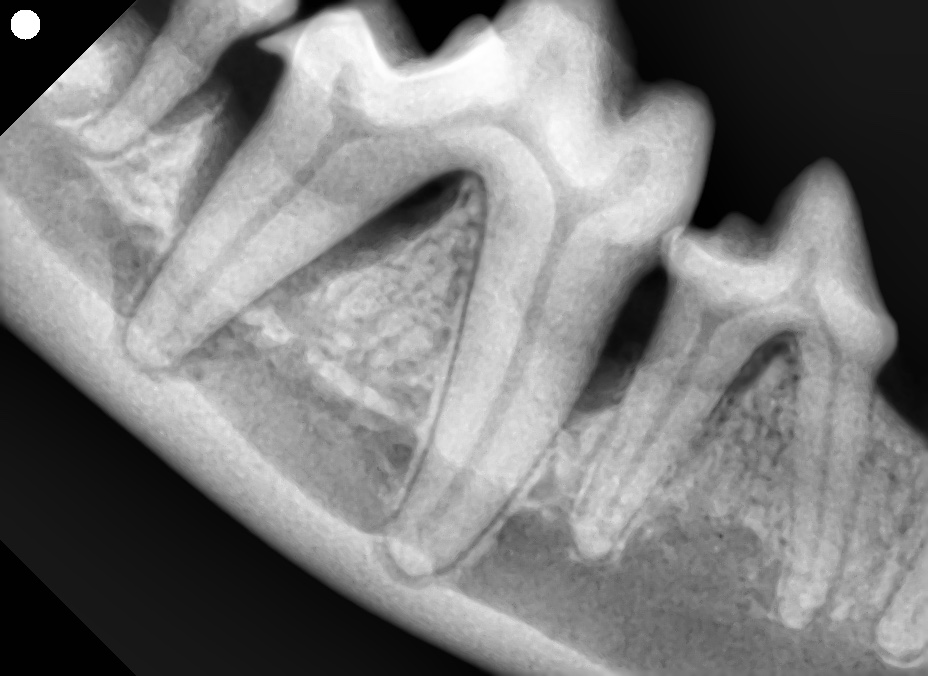

一見すると大きな異常はなく、歯も綺麗に見えます。飼い主さまも驚かれていましたが、全身麻酔下での歯科用レントゲンで右下顎第一後臼歯に進行した歯周病が確認されました。

この歯は食べる時にとても大切な「機能歯」であり、年齢もまだ若いため、第一後臼歯は抜歯ではなく保存治療を選択しました。

また、治療後の骨再生を阻害してしまう可能性があるため周囲の非機能歯(第四前臼歯及び第二後臼歯)は抜歯しました。